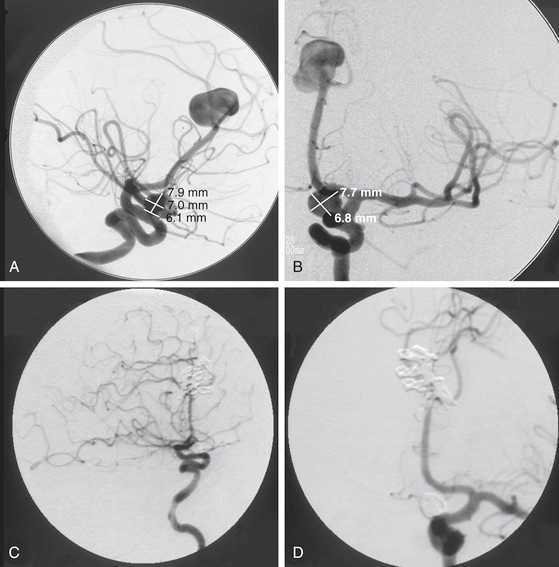

一名67岁的患有慢性头痛的女性接受了左颈动脉造影,发现其斜(A)和前-后(A)直径为1.5 cm的Azygos ACA动脉瘤和7 mm的眼科动脉瘤。(B)视图为眼动脉瘤被盘绕,而双侧开颅和前半球间入路夹住了ACA动脉瘤。术后外侧(C)和AP(D)投影血管造影上未见残留动脉瘤。